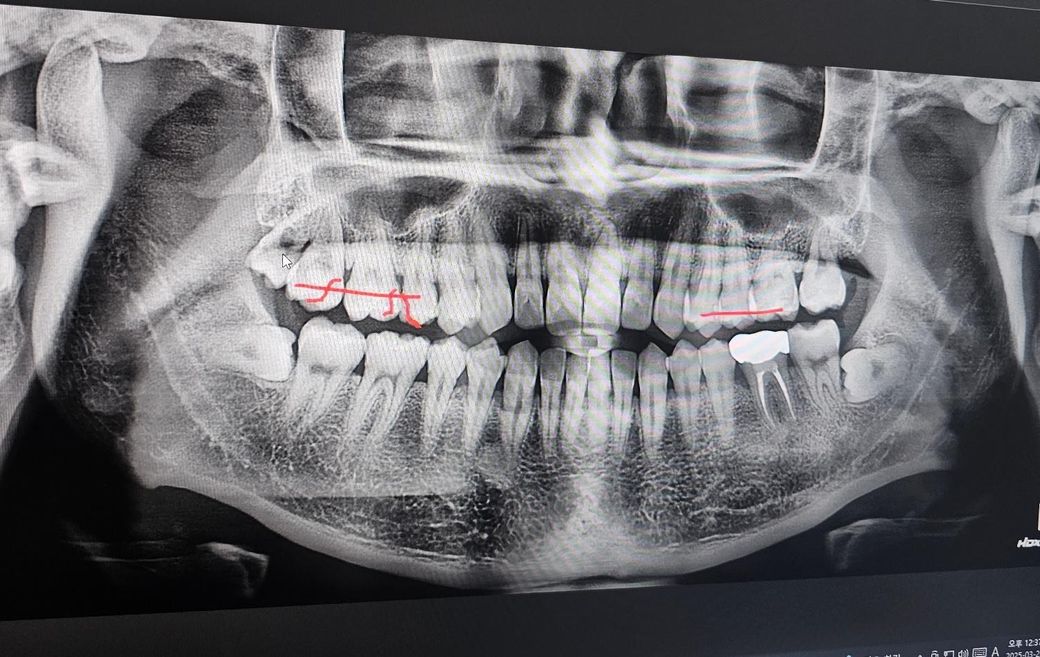

인접면충치 전문가분들의 의견이 궁금합니다

크라운5개+인레이4개(4개중3개는 크라운권장)+레진+잇몸치료+윗쪽 왼쪽 사랑니 발치

대부분 레진 인레이(그중 하나는 크라운할수도) +잇몸치료+사랑니발치

첫번째병원에선 즉 크라운7~8개를 하라고하셨는데 내이빨을 너무 많이 갈아내야 하는게 아닌가... 싶고

두번째병원에선 의사마다 견해와 처방이 다르다 이전병원은 충치인지 아닌지 약간만 의심되도 일단 갈아내고 없애야한다는 판단인거같다고 말씀하셨고 두번째병원에서는 인접면충치가 확인하기 힘들 뿐더러 갈아냈는데 충치가 아닐수도있다~ 라고 애매모호하게 말씀하셨어요

• 1번 째 사진